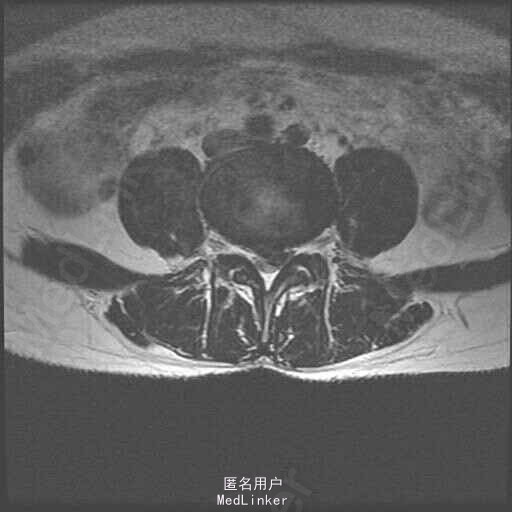

主诉:左下肢疼痛伴腰痛1月 病史:患者女性,39岁,十月前无明显原因发生腰痛,休息后缓解。未做其他治疗,1月前,出现左腿放射性疼痛,外侧及足后为主,腰部酸胀,无麻木等异常感,腰部活动障碍,不能正常行走,发病来大小便正常。在外院行ct检查后,诊断为腰椎间盘突出,未见影像片。

查体:脊柱无侧弯,腰部叩痛,活动障碍。上肢肌力感觉均正常。左下肢疼痛伴稍麻木感,肌力可,跟膝腱反射正常,直腿抬高试验:左侧55度,右侧35度,病理征未引出。 辅助检查:x线见腰椎退行性改变 MRI:L4-5,L5-S1椎间盘突出

诊断:L4-5,L5-S1椎间盘突出 治疗;患者神经压迫症状是由L4-5节段椎间盘突出所致,手术主要对L4-5节段减压,后固定。